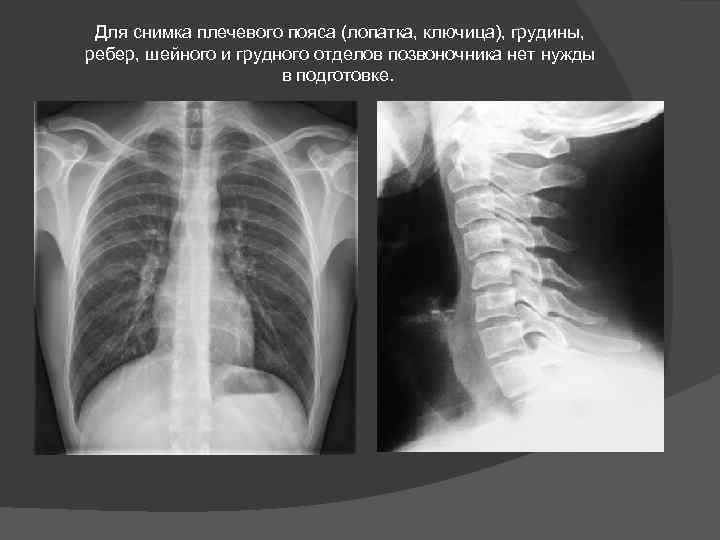

Для снимка плечевого пояса (лопатка, ключица), грудины, ребер, шейного и грудного отделов позвоночника нет нужды в подготовке.